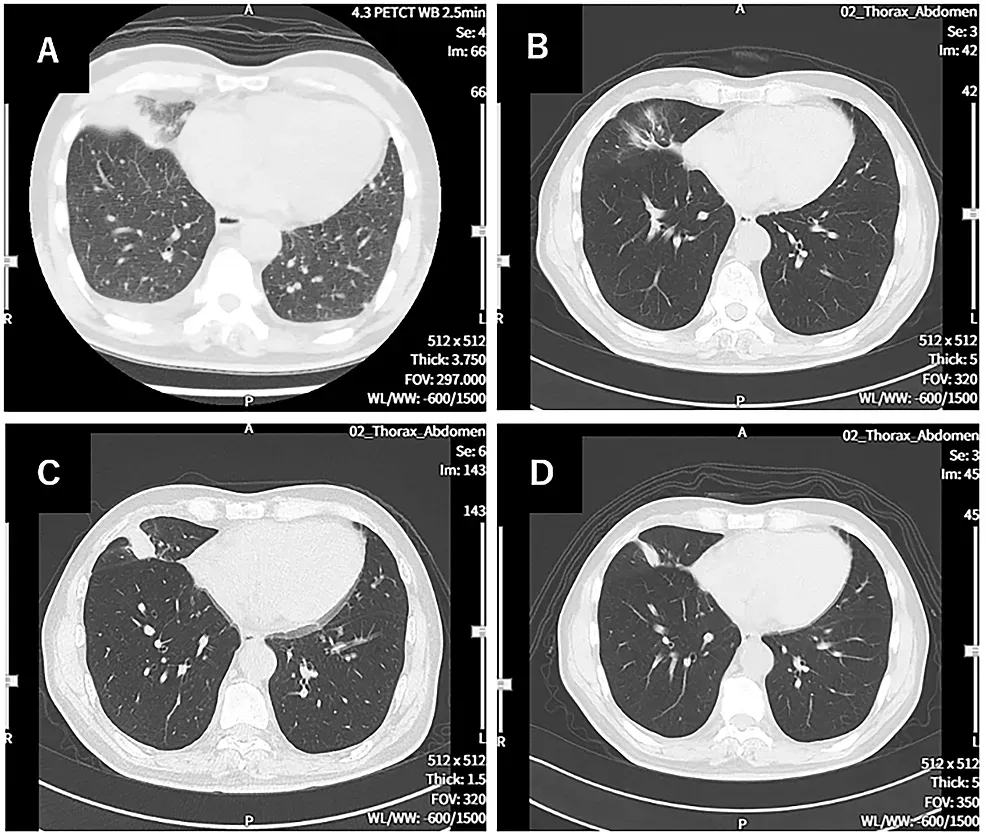

树突状细胞(DC)疫苗疗法,核心是通过呈递癌症抗原增强患者抗肿瘤免疫力。《Cureus》报道过WT1-DC疫苗治疗晚期肺癌的显著疗效案例:69岁男性确诊右肺中叶IV期鳞状细胞癌,因不耐受手术及放疗,接受WT1-DC疫苗+紫杉醇+卡铂AUC6化疗联合治疗。

治疗获益明确:CT显示,治疗前右下肺原发灶伴胸腔积液,114天后原发灶几乎消失;213天出现复发迹象,338天后复发灶缩小(详见下图)。PET-CT显示,治疗前除原发灶外,双侧肺、骨、肝多发转移,479天后仅残留右肺2个1.0cm病灶、肝脏1个1.7cm小转移灶,无新增转移。最终患者临床状态良好,PS评分为1分,可正常生活!

▲图源“Cureus”,版权归作者所有,如无意中侵犯了知识产权,请联系我们删除